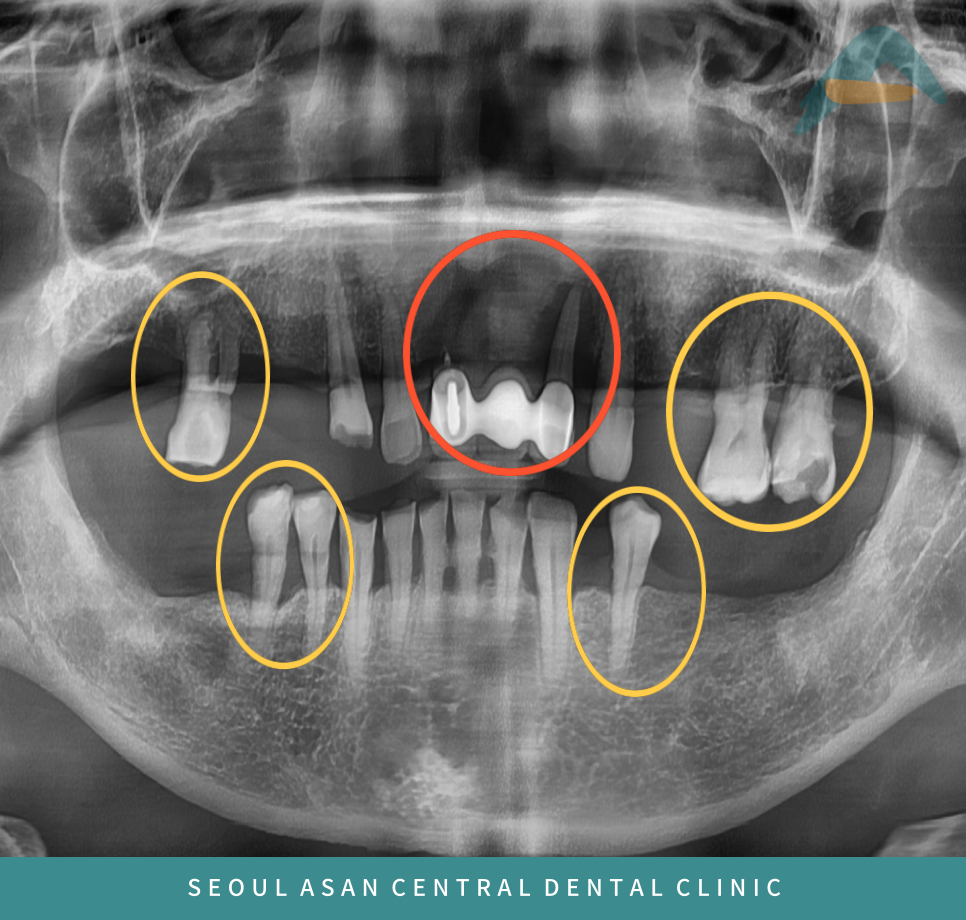

일부 치아는 이미 상실된 상태였으며,

남아 있는 잔존 치아들에서도 동요도가 관찰되었습니다.

이에 치료를 진행하기 전

파노라마 방사선 촬영을 통해

전반적인 구강 상태를 정밀히 파악한 후

치료 계획을 수립하는 것이 필요합니다.

특히 상악 전치부의 기존 보철물이 장착된 부위와

상·하악 양측 구치부의 잔존 치아들에서

동요도가 심한 경우,

해당 치아를 장기간 유지하기는 어렵다고 판단될 수 있습니다.

이러한 경우 예후가 불량한 치아들은 발치가 필요할 수 있습니다.